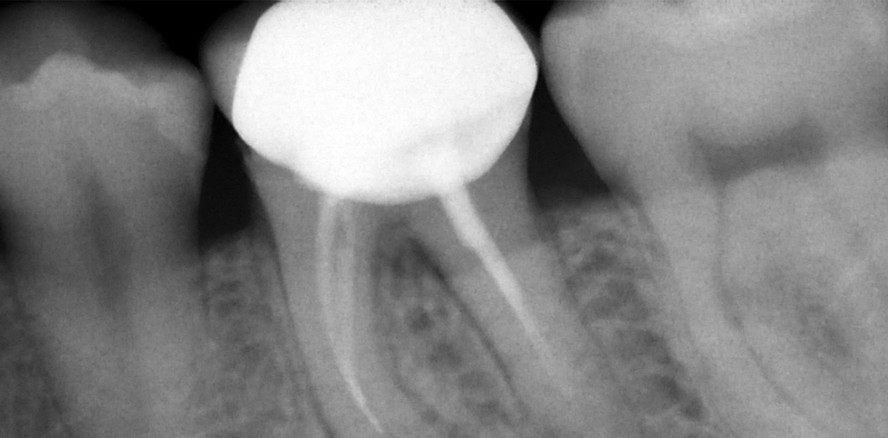

Zuerst wurde das Fragment mit Ultraschall entfernt und die Perforationsdeckung mit TotalFill® BC RRM durchgeführt. Nach Erstellung eines manuellen Gleitpfades mit Handfeilen ISO 008 und 010 sowie elektronischer Längenmessung (Root ZX, J. Morita, Japan) wurde ergänzend ein maschineller Gleitpfad (PathFiles®, Dentsply Maillefer) instrumentiert. Danach erfolgte die weitere mechanische und chemische Desinfektion beider Zähne unter Verwendung von Handinstrumenten und maschineller Aufbereitung mit einem flexiblen NiTi-System (XP-endo® Shaper, FKG, Schweiz) und ultraschallaktivierter Desinfektion mit 5,25%igem NaOCl unter dem Operationsmikroskop (OPMI PROergo®, Zeiss, Oberkochen). Abbildung 4 zeigt das Abschlussbild nach Wurzelkanalfüllung mit TotalFill® BC Sealer™. Auf den Recall-Bildern nach sechs Monaten und 1,5 Jahren ist der Verlauf mit vollständiger Ausheilung der apikalen Läsion ersichtlich (Abb. 5 und 6).